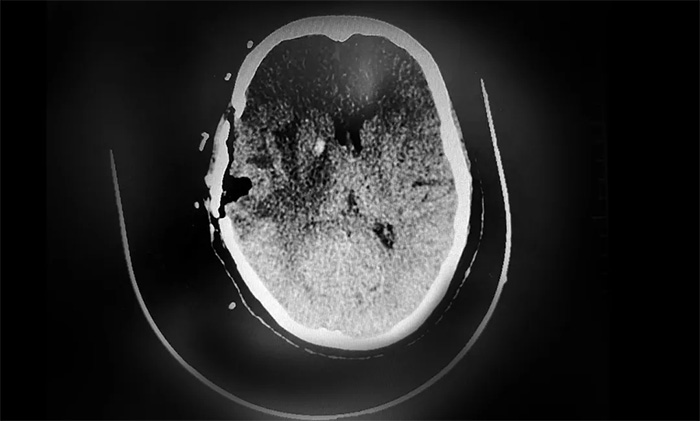

經(jīng)過與患者家屬充分溝通治療方案并取得同意后,盧云鶴博士為患者開展了神經(jīng)導(dǎo)航下顱內(nèi)病灶切除術(shù),在切除右側(cè)顳葉腫瘤緩解占位壓迫癥狀的同時(shí),留取部分腫物送檢,評(píng)估病理狀態(tài)。

▲ CT復(fù)查示,腫瘤已被切除

根據(jù)初步病理檢測(cè)報(bào)告,送檢的樣本為顳葉轉(zhuǎn)移癌,結(jié)合病史及免疫組化,符合乳腺癌轉(zhuǎn)移。后續(xù),盧云鶴博士將根據(jù)分子病理檢測(cè)結(jié)果,為患者制定實(shí)施包括靶向治療等多學(xué)科聯(lián)合的個(gè)體化綜合治療方案,改善患者生存狀態(tài),延長(zhǎng)生存期。